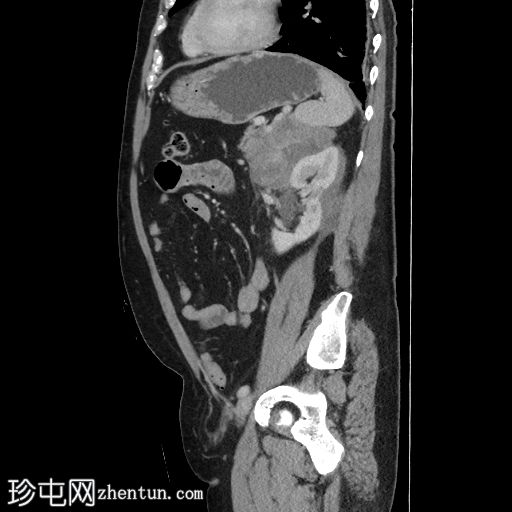

矢状位增强扫描(门静脉期)

右肾可见不规则分叶状低密度浸润性病变,超出肾包膜,并与右肝下叶相邻。

左肾可见弥漫性浸润性病变,以上极为中心。左肾浸润性病变与胰尾相邻,胰尾可能受累,表现为胰腺后缘不规则、脂肪间隙消失。此外,浸润性病变与左侧肾上腺外侧肢相邻。